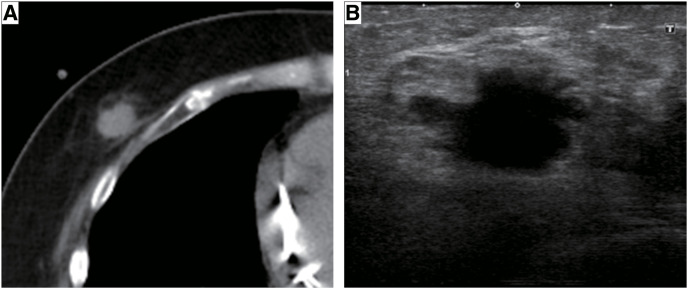

CASE PRESENTATION: A 52-year-old woman was referred to our hospital and was subsequently diagnosed with bilateral breast cancer. Computed tomography (CT) and magnetic resonance imaging incidentally detected a liver tumor in the hilar region and lymph node enlargement in the hepatoduodenal ligament. A 19 mm tumor was observed in the area surrounded by the right and left branches of the portal vein and an abnormal portal branch of segment 7. Positron emission tomography-CT showed fluorodeoxyglucose uptake in the liver tumor, hepatoduodenal ligament lymph nodes, and bilateral breasts. A tumor biopsy showed a papillary tumor, and ICC was suspected. As ICC with LNM has a poor prognosis, neoadjuvant chemotherapy was planned. Genetic testing using a blood sample revealed a BRCA2 mutation, indicating the patient would benefit from chemotherapy, particularly cisplatin. The patient received a chemotherapy regimen comprised of gemcitabine, cisplatin, and S-1 (GCS), and after 7 courses, her carbohydrate antigen 19-9 level decreased from 2433 to 15 U/mL. CT showed that the tumor had shrunk and the LNMs were indistinct. The patient was referred to our department for curative surgery, which included a left hepatectomy, caudate lobectomy, hepatoduodenal ligament lymph node dissection, bile duct resection, and choledocojejunostomy. The postoperative course was generally uneventful, and the patient was discharged on postoperative day 18. Pathological examination of the resected specimen revealed an absence of malignant cells. At 24 months postoperative, there was no evidence of recurrence.